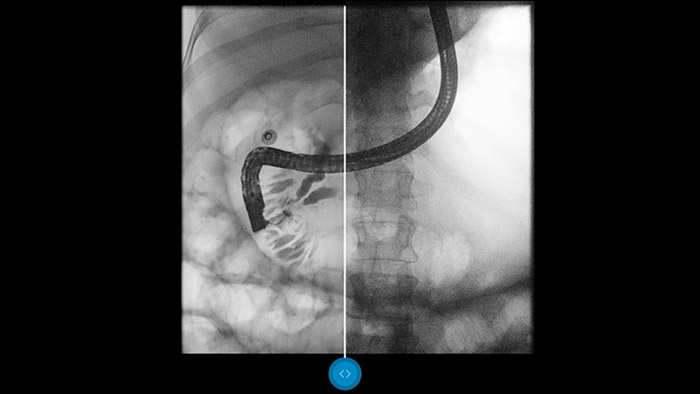

Сравните с традиционной обработкой в режиме параллельного просмотра изображений и сами убедитесь в преимуществах этой технологии.